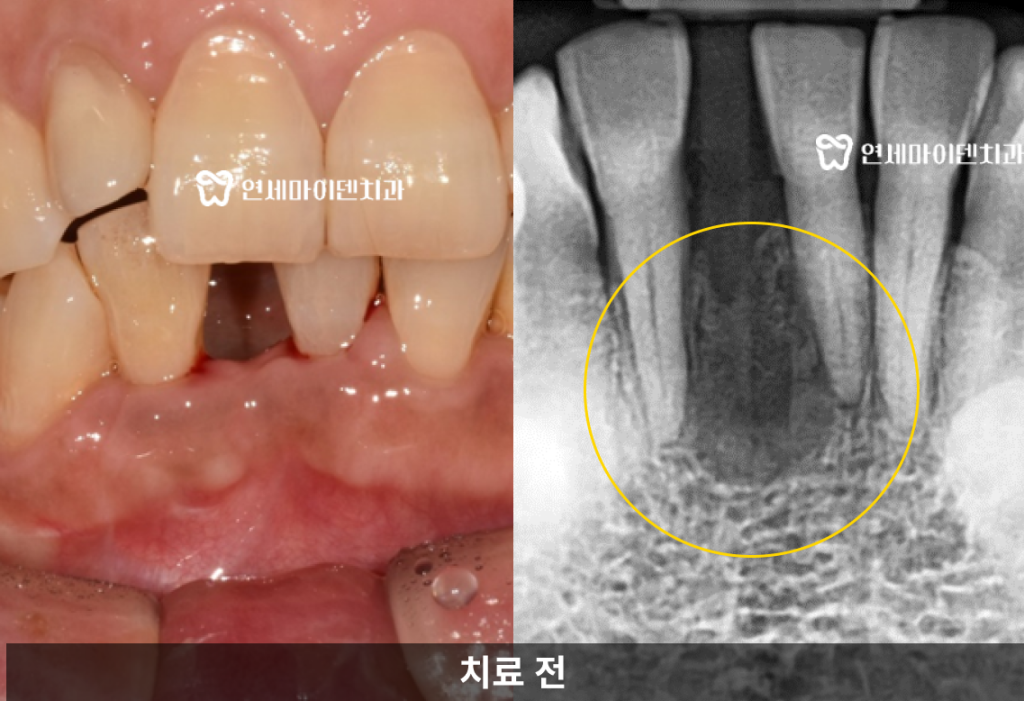

진단 결과, 문제는 기존 신경치료가 완전하게 이루어지지 않아서

치아 뿌리 끝에 염증이 남아있었고그로 인해 뿌리 중간 부위의 치조골이 녹아 있는 상태였습니다.

이러한 경우는 치아에 금이 가 있을 가능성도 높기 때문에

단순한 재신경치료만으로는 치료가 어려울 수 있습니다.염증으로 녹은 뼈, 살릴 수 있을까?

잇몸 뼈가 흡수되고 잇몸 형태도 무너지게 됩니다.실제로 이 환자분의 경우

발치 부위의 잇몸 뼈가 아직 회복되지 않은 채

엑스레이 상으로 까맣게 흡수되어있는게 보입니다.양옆 치아 뿌리에도 영향을 줄 수 있는 상태였습니다.